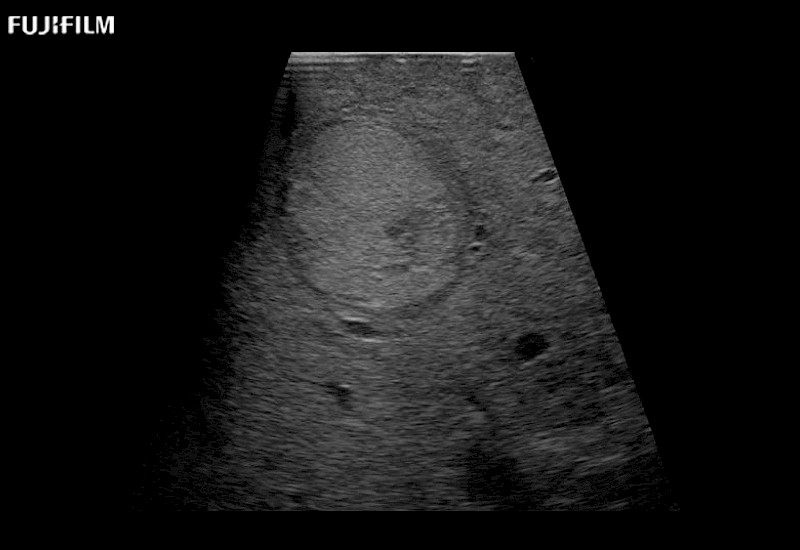

The ARIETTA 750 incorporates all of the proven technologies and functions that medical professionals have come to expect from Fujifilm Healthcare.

ARIETTA 750 is the definitive diagnostic ultrasound solution for any clinical setting - Private Office, Imaging Center, or Hospital. The ARIETTA platform provides the ultimate in clinical performance with its state-of-the-art features and large user-friendly display.

The ARIETTA 650 DI combines trusted Fujifilm Healthcare technologies and features tailored for surgical oncology.

Designed to meet the demands of surgeons, the ARIETTA 650 DI offers precise guidance. Its advanced capabilities and large, intuitive display offer accurate and efficient care in operating rooms and specialized surgical settings.